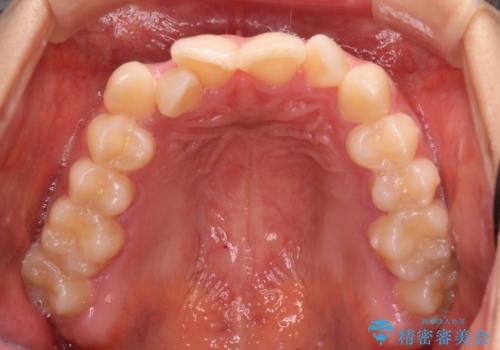

抜かない矯正 審美装置によるワイヤー治療

- 前歯のガタガタを主訴に来院されました。